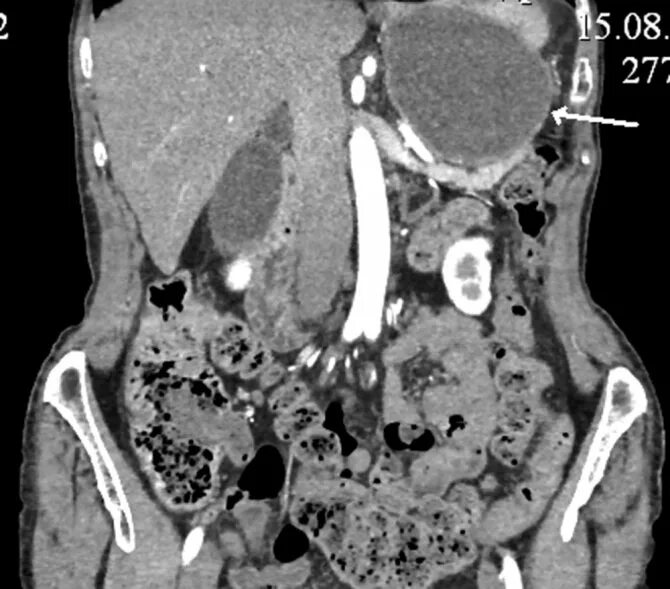

Язва желудка кт